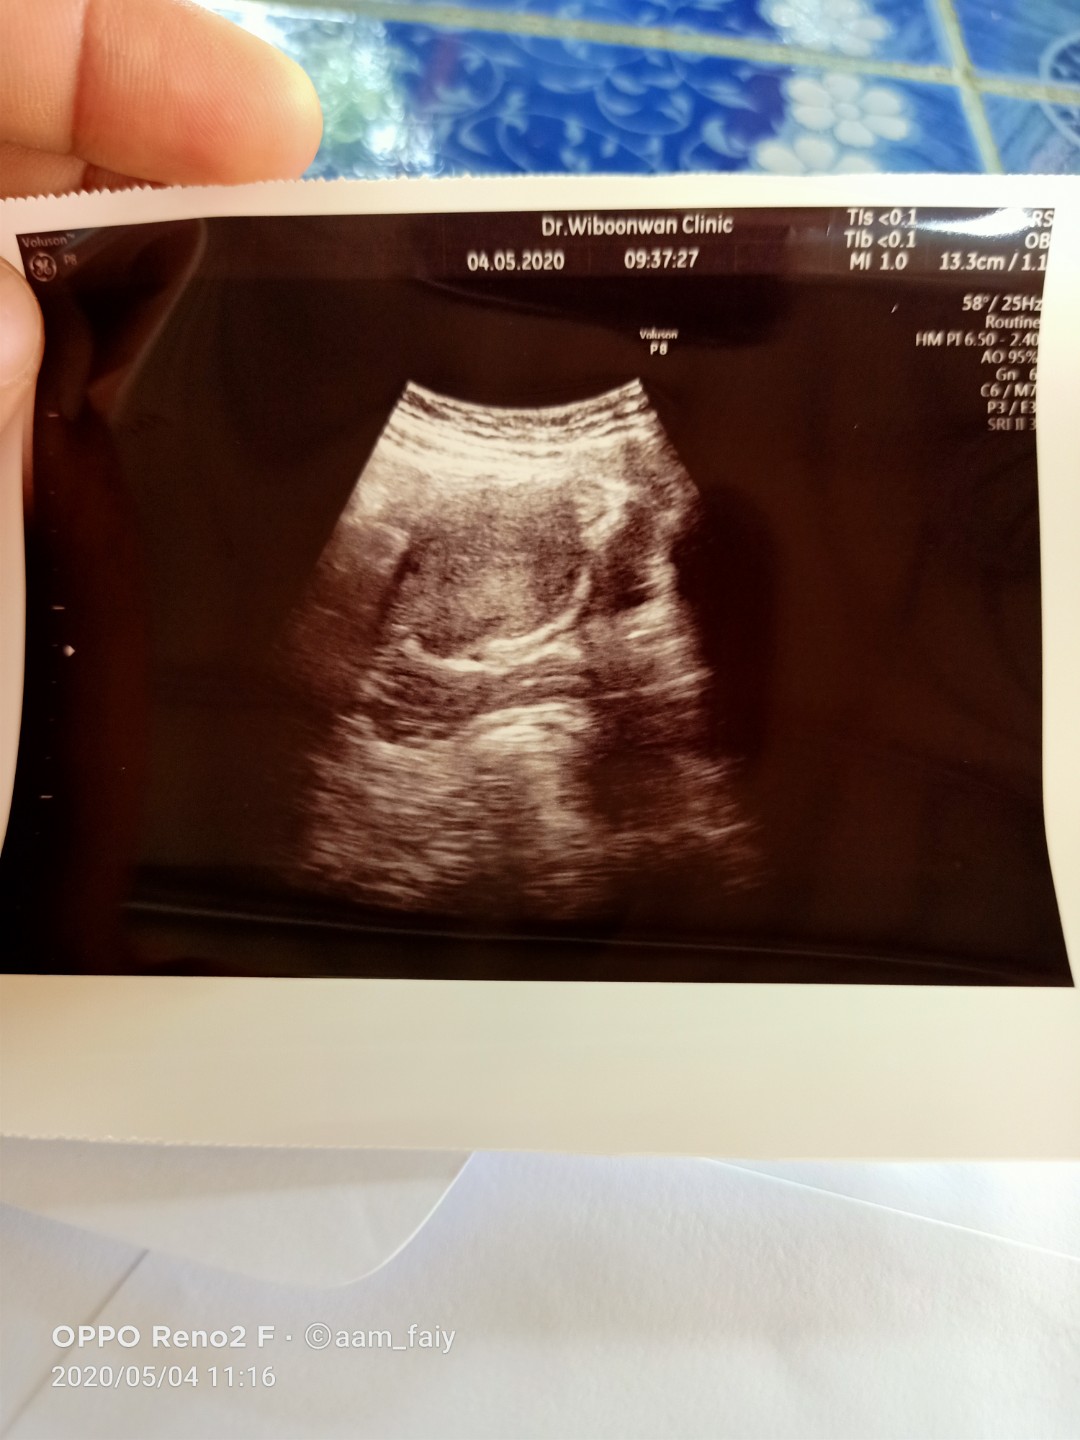

บ้านนี้ เจอถุงตั้งครรภ์เล็กๆเองค่ะ ตอน 4w4d ตามภาพค่ะ เจอถุงตั้งครรภ์กลมๆ ตอน 6w5d เจอน้องและเสียงหัวใจน้องตอน 13w1d